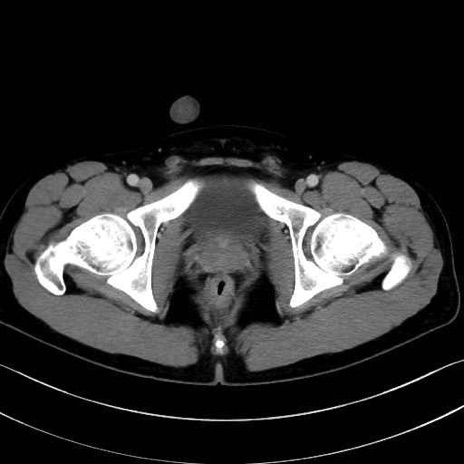

肛門挙筋(levator ani muscle)のCT画像の解剖

肛門挙筋 (Levator ani)